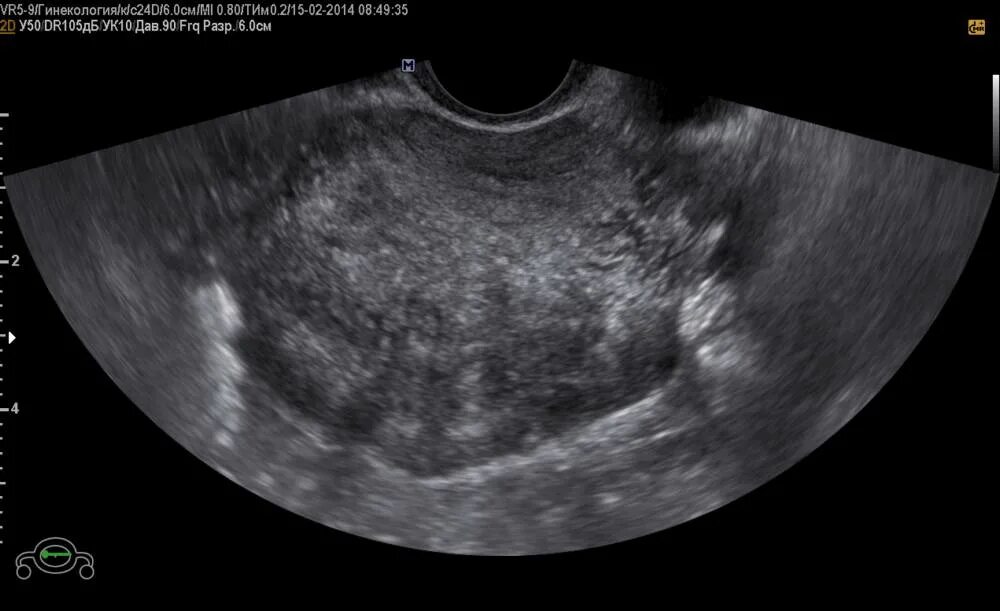

Что такое аденомиоз 1 степени у женщины